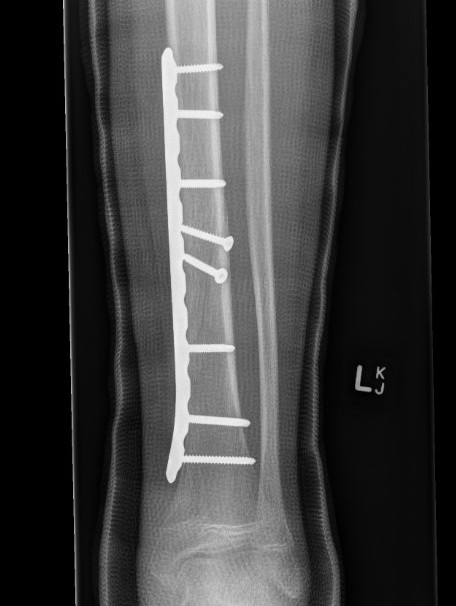

Fixation

- Grade I - reduced +/- percutaneous pinning, long leg cast once wound closed

- Grade II & III - external fixation